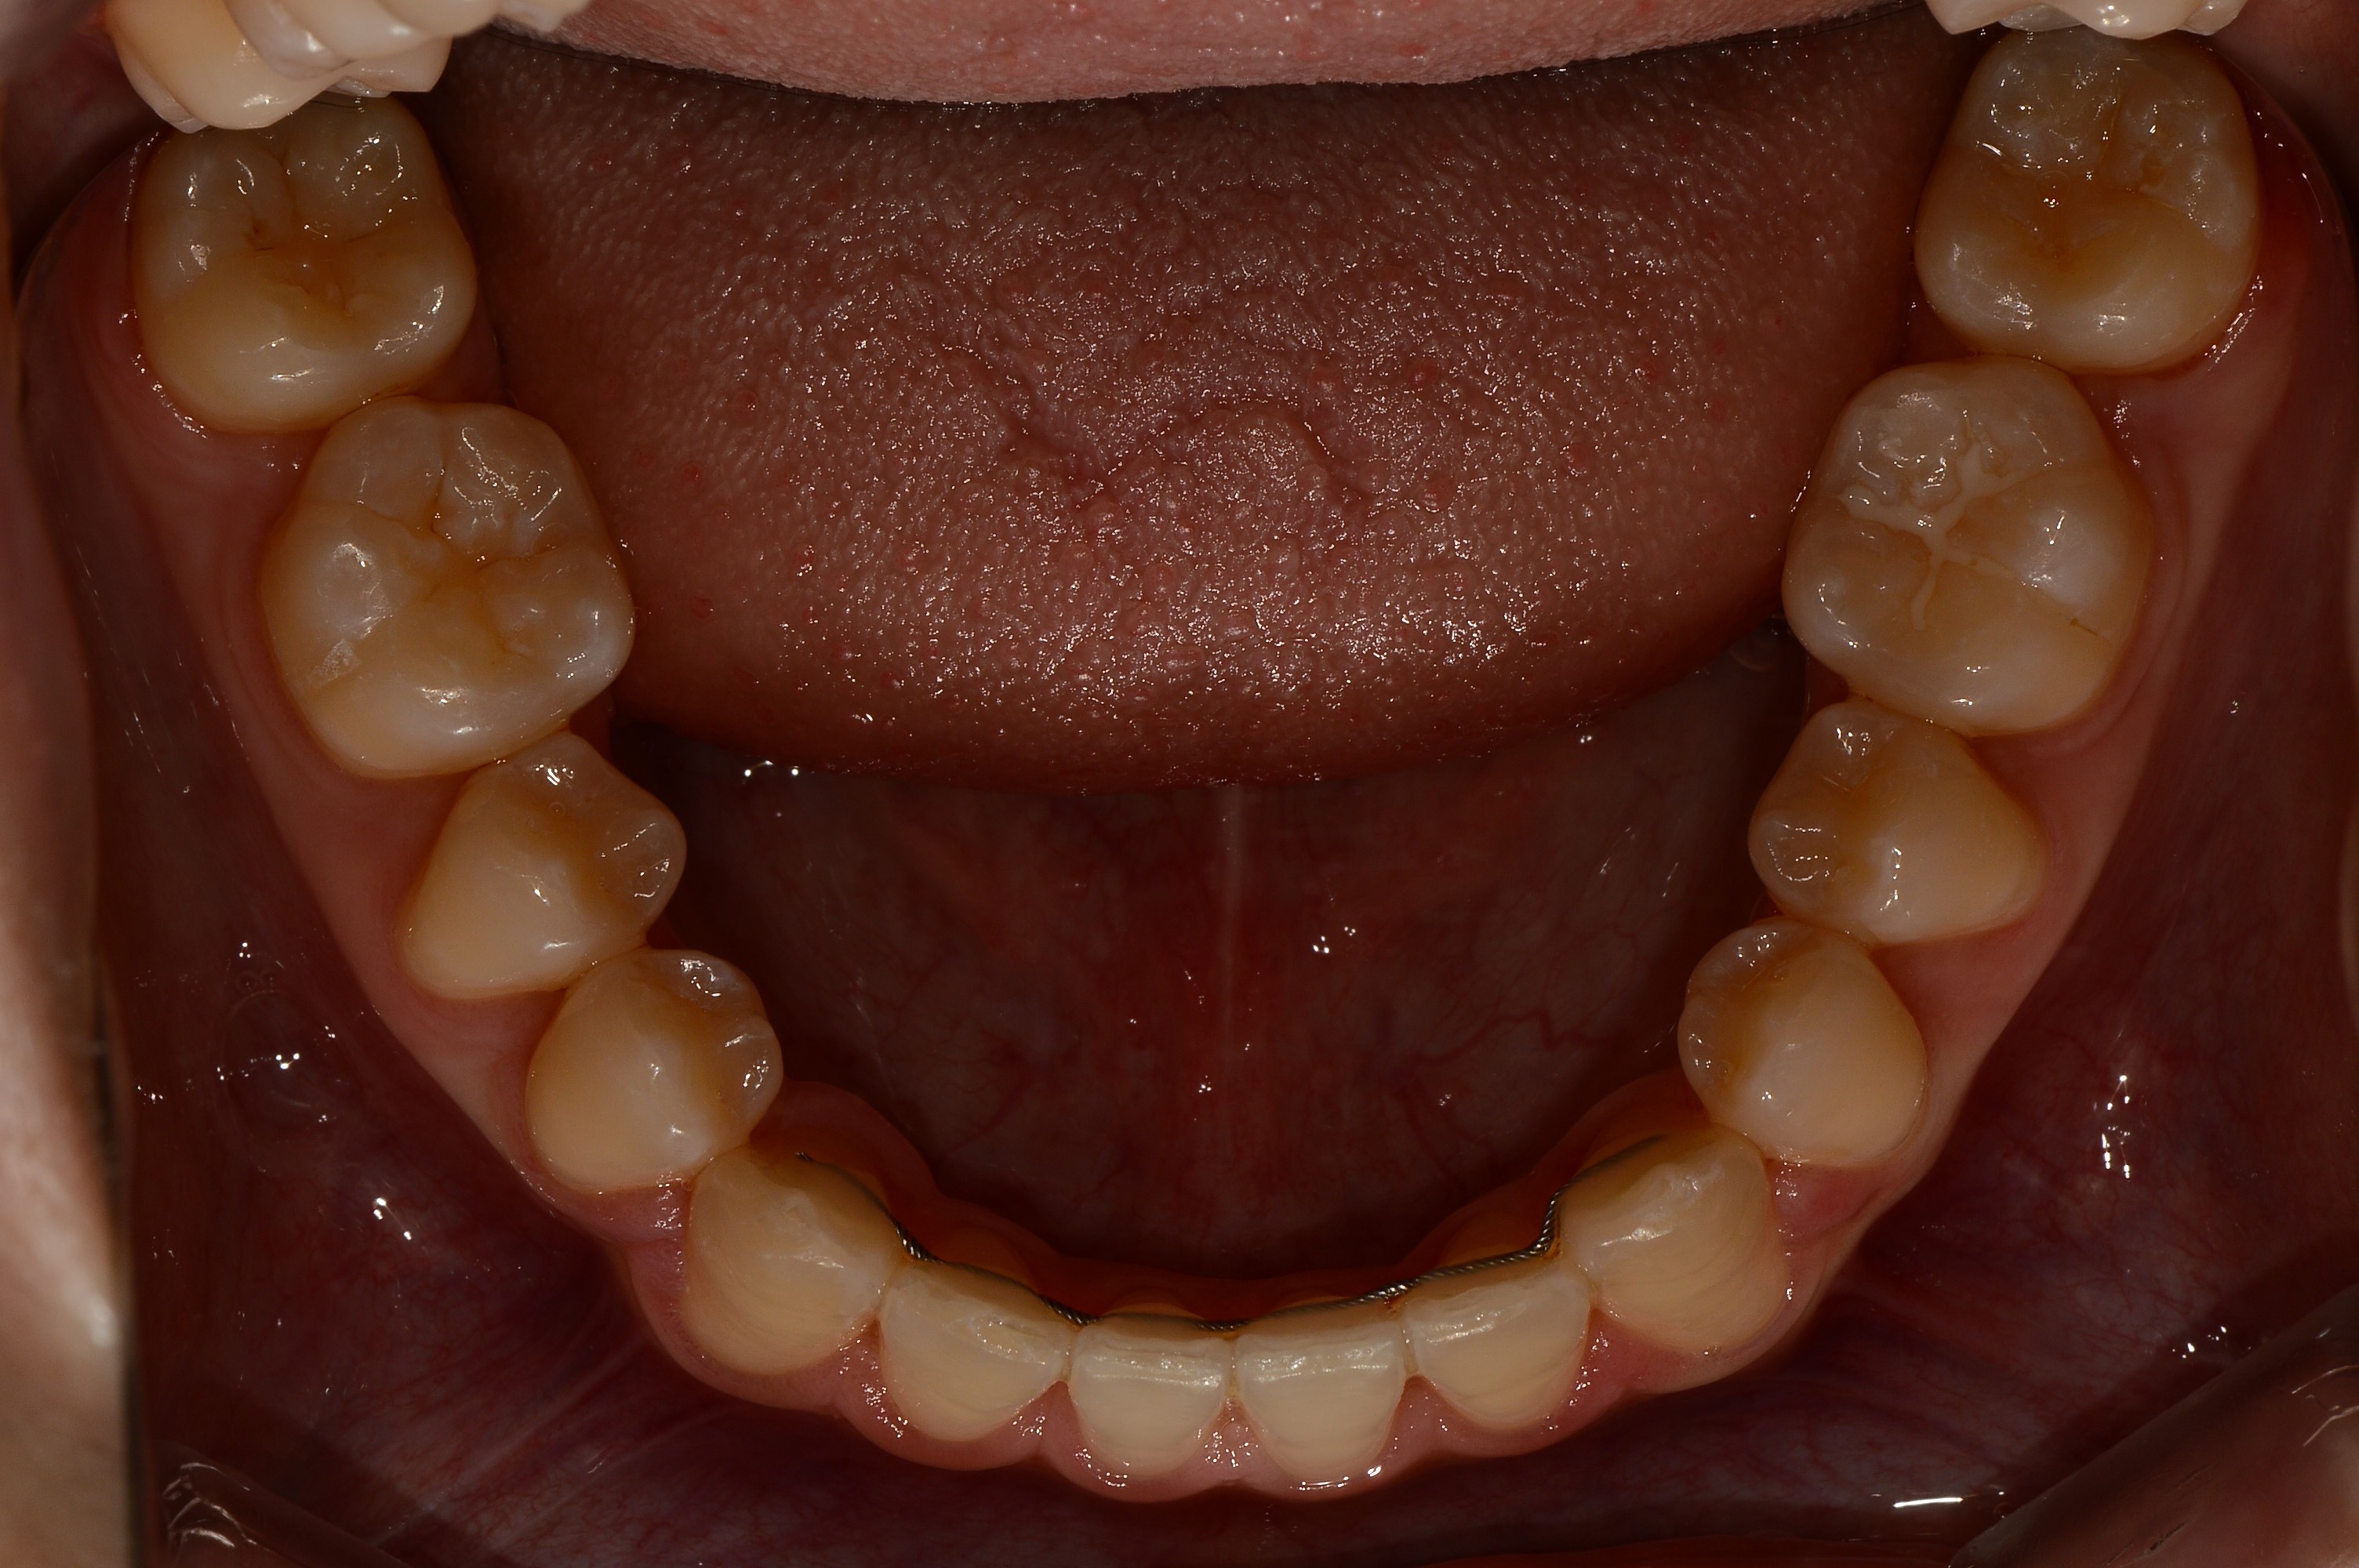

치료 전 사진입니다.